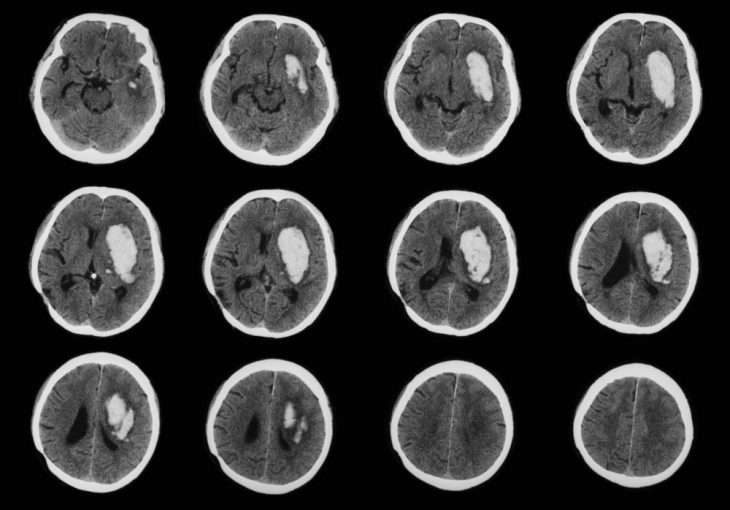

Современные методы исследования (МРТ, КТ) зачастую помогают врачу установить точный диагноз, но иногда и они оказываются малоинформативными. При исследовании головного мозга пациента на снимках визуализируются области затемнения, объёмные образования, свидетельствующие об:

- Опухоли. Она может быть доброкачественной, злокачественной. Нередко в головном мозге обнаруживают метастатические очаги (чаще при раке лёгких). Биопсия необходима для диагностики глубоко расположенных опухолей. Её рекомендуют при подозрении на распространённую диффузную глиому.

- Абсцессе или гематомах. Их трудно дифференцировать на КТ- и МРТ-снимках от других новообразований.

Если с помощью КТ и МРТ не удалось установить точный диагноз, особенно если необходимо дифференцировать опухоли от других заболеваний (кровоизлияния, абсцесса, поражения паразитами, лейкоэнцефалопатии, инфаркта головного мозга, метастазов опухолей другой локализации, сосудистых мальформаций, рассеянного склероза) и между собой, назначают биопсию.